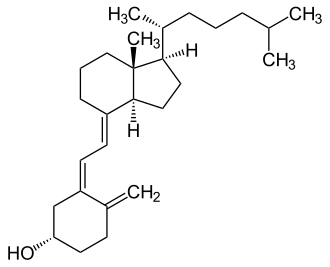

| Name | Chemical composition | Structure |

|---|---|---|

| Vitamin D1 | Mixture of molecular compounds of ergocalciferol with lumisterol, 1:1 |   |

| Vitamin D2 | ergocalciferol (made from ergosterol) |

|

| Vitamin D3 | cholecalciferol

(made from 7-dehydrocholesterol in the skin). |

|

| Vitamin D4 | 22-dihydroergocalciferol |

|

| Vitamin D5 | sitocalciferol

(made from 7-dehydrositosterol) |

|

Several forms (vitamers) of vitamin D exist, with the two major forms being vitamin D2 or ergocalciferol, and vitamin D3 or cholecalciferol.[1] The common-use term "vitamin D" refers to both D2 and D3, which were chemically characterized, respectively, in 1931 and 1935. Vitamin D3 was shown to result from the ultraviolet irradiation of 7-dehydrocholesterol. Although a chemical nomenclature for vitamin D forms was recommended in 1981,[13] alternative names remain commonly used.[3]

Chemically, the various forms of vitamin D are secosteroids, meaning that one of the bonds in the steroid rings is broken.[14] The structural difference between vitamin D2 and vitamin D3 lies in the side chain: vitamin D2 has a double bond between carbons 22 and 23, and a methyl group on carbon 24. Vitamin D analogues have also been synthesized.[3]